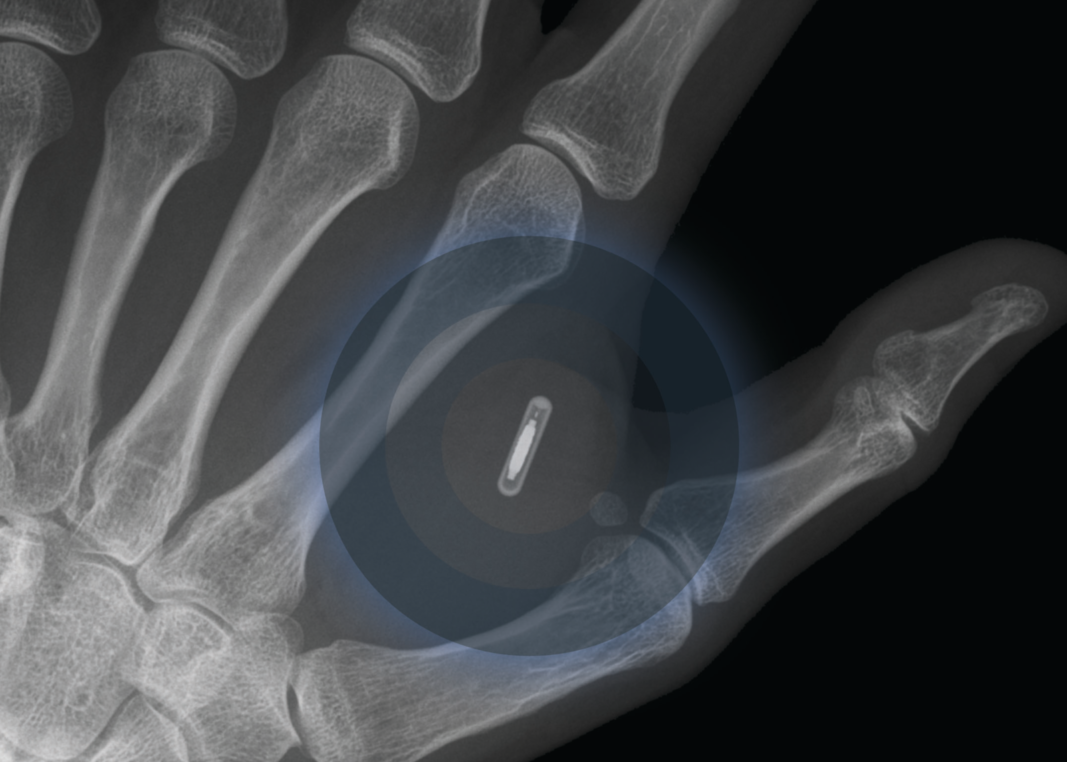

Hand With Implantation Of Micro Chip. XRay View Closeup. Chipization Microchips In Your Hand it's a useful technology application: Overall, the hand surgeon should be aware that these. you can now get a payment chip injected beneath your skin, turning you into a human bank card. Here's a story of a us tech company named 32m that implanted. ever heard of microchips in humans. the company, called walletmor, is selling. Microchips In Your Hand.